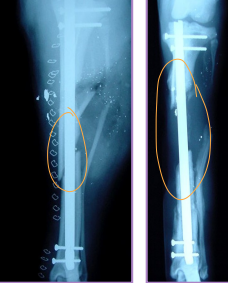

Interlocking Nail

What: IM pin + locking bolts proximal and distal

IM pin controls bending

Bolts control shear & rotation

Why: femur, tibia, humerus: limited to

$$, technically demanding, specialized

How:

Fills 80-90% of medullary canal

Place proximal and distal of break

Diaphyseal fractures (#1)

Tx: plate + screws, interlocking nail, IM pin + cerclage

Tibia & fibula Fractures

Sx: Plate + screws, IM pin + cerclage, Interlocking nail, ESF